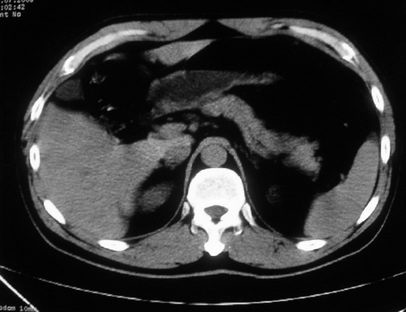

男,体查发现右肝低密度,右肾高密度结节影。高密度ct值92hu,囊肿?

肝右叶囊肿或血管瘤?右肾高密度囊肿。建议增强。

肝右叶圆形低密度灶,考虑囊肿或血管瘤,建议ct增强检查;右肾包膜下高密度圆形灶,考虑:囊肿并出血